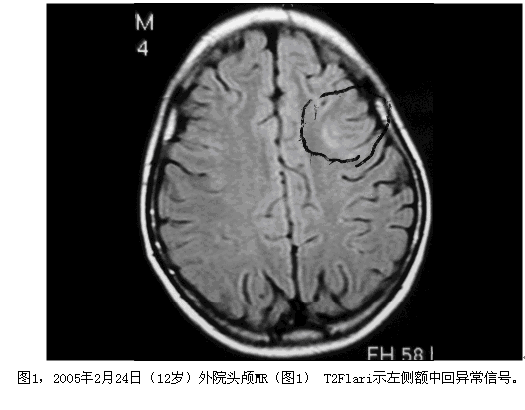

患者女性,21岁,11岁开始发作,表现:眼前出现黑色的实心圆点或黑色的正方形,双眼向右凝视带动头向右侧偏转,曾有一次伴转圈,双手握拳僵硬,严重时意识不清,仅有一次伴四肢强直阵挛,类似发作频率:从3次/月增至每日无数次,清醒、睡眠中均有发作。最长间歇期:2-3年(14岁-17岁年无发作)。曾服用土方(具体不详)。现服用奥卡西平(仁奥)300mg/早、晚;德巴金500mg/早、晚;拉莫三嗪50mg/次,每日2次;左乙拉西坦500mg/次,每日2次。2014年7月16日癫痫发作时跌倒,后头部着地,昏迷数分钟,鼻、左耳流血。

患者考虑为药物难治性癫痫,且曾有发作致脑外伤的事件,纳入术前评估。结合相关检查结果,脑电图报告:异常脑电图III(清醒/睡眠),间歇期:弥漫性,左额-中央著,发作期:临床:右侧偏转。EEG:发作型,左半球。头颅MRI薄层扫描:1.右侧颞叶皮层(含颞极)、邻近右侧额下回多发软化灶并胶质增生、含铁血黄素沉着;右侧额叶眶回局部慢性小出血灶并含铁血黄素沉着可能性大;2.待排左侧额上回与额下回交界处局灶性脑皮质发育不良;3.考虑左侧乳突炎症改变。视野检查无异常。韦氏测试:智商84,言语76,操作96,记忆<51。癫痫定位考虑为额叶外侧面,定侧为左侧,病因考虑皮层发育不良;经全中心讨论后计划一次性切除手术,切除范围,后界:中央前沟后壁,上界:额上沟外侧壁,下界:额下沟外侧壁1cm;前界:额中回后部。予术中唤醒下切除,切除过程中嘱患者讲话并交流,病变质地稍硬,将病变全部切除,约3.5*3.0*3.0cm,术后患者无语言功能障碍,随访近3个月无发作,术后病理回报:局灶性皮层发育不良FCD Ib型。